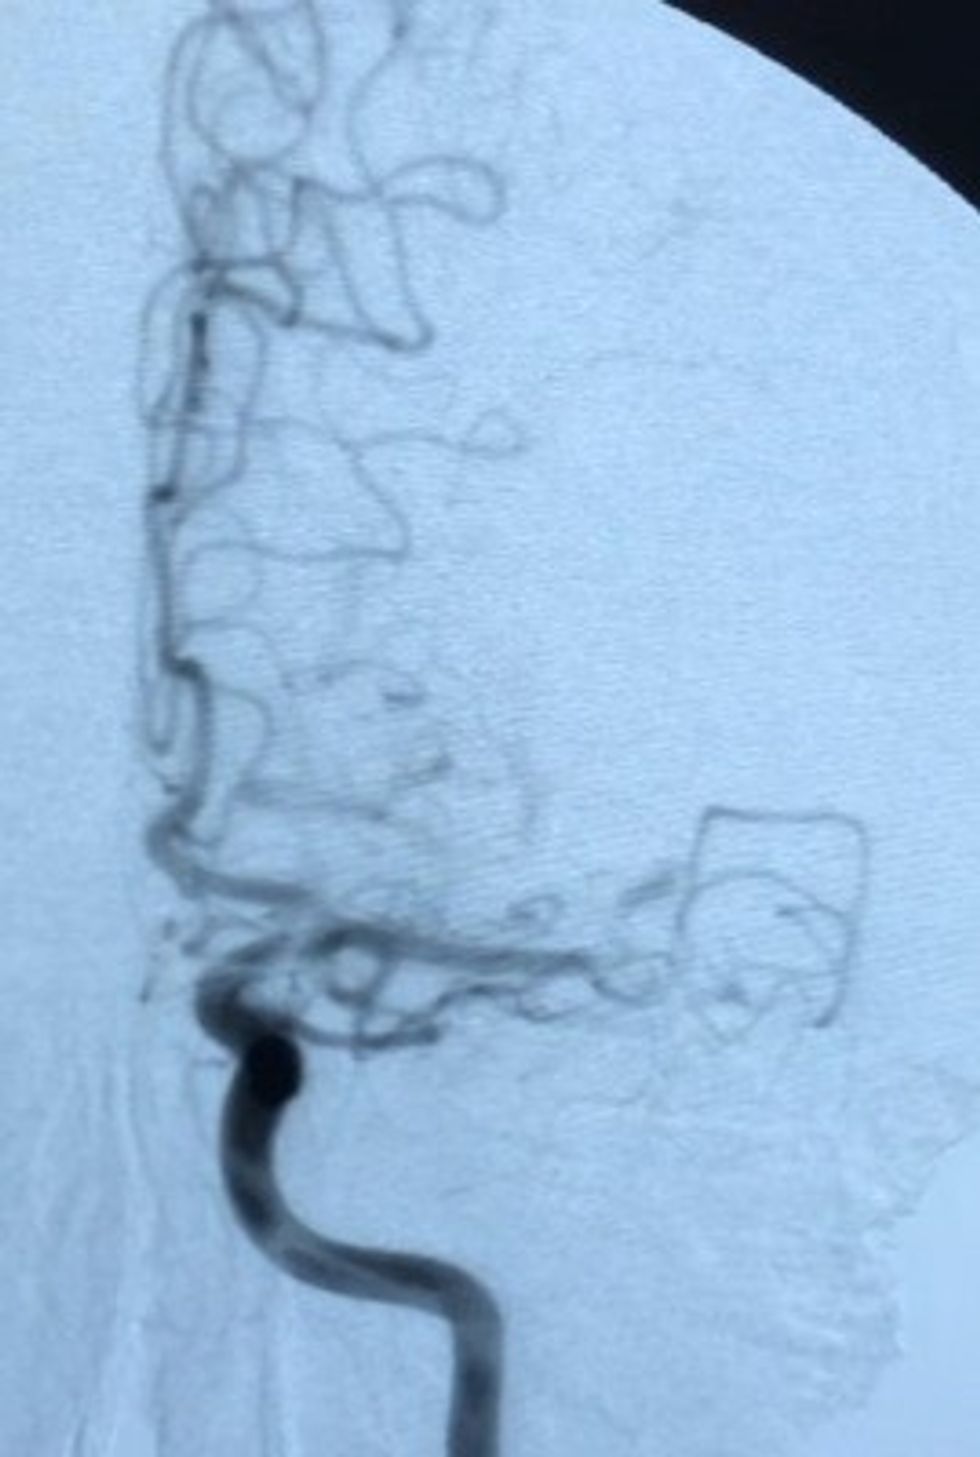

Për herë të parë në kuadër të Qendrës Klinike Universitare të Kosovës, Klinika e Radiologjisë, ka realizuar heqjen e gjakut të ngjizur në arterien e trurit në mënyrë mekanike (trombektomia mekanike e M2 segmentit të arteries cerebri media majtas) me metodë radiologjike neurointervente minimale invazive.

"Procedura u krye pa komplikime, tek pacienti mashkull i moshës 62 vjeç, i cili kishte dorën e palëvizshme dhe këmbën e djathtë të dobësuar, pas procedurës i është kthyer menjëherë lëvizshmëria e dorës së djathtë.

Poashtu, të folurit e humbur në tërësi, kurse pas 12 orëve nga kryerja e procedurës, pacienti ka filluar të artikuloj zë dhe lëvizë lirshëm edhe me këmbë.", thuhet në njoftimin e QKUK-së.

:Brenda 3 apo 4 orëve pas sulmit në tru, procedurën e kanë realizuar ekipi i radiologëve, Dr. Bujar Gjikolli, Dr. Arben Kutllovci, përkrahur nga radiologët kujdestar Dr. Agron Arifi, Dr. Ilir Bejta, me referimin e neurologëve kujdestar Dr. Rushit Jashari, Dr. Valbona Spanca e Dr. Milaim Krasniqi, me asistimin e teknikëve të radiologjisë Shekfi Bytyqi, Ariana Neziri.